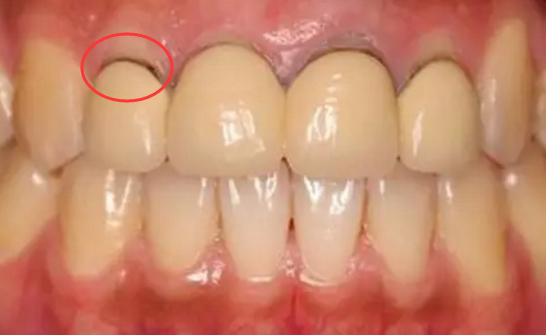

自信的笑容源自一口整齐的牙齿,可一旦门牙缺失就会打破一口整齐的牙齿,笑容大打折扣,还会让人颜值下滑,说话的时候也会出现漏风的问题,的确很容易让人尴尬,那门牙缺失该如何解决呢?

温州蓝芽的医生指出,门牙缺失有两种修复方式可以选择,一种是烤瓷牙,另外一种是种植牙,而在这两者方面选择,更推荐的是种植牙,单单从两者的修复方式来看,种植牙更胜一筹,烤瓷牙是通过磨损两颗健康的邻牙做支撑点,然后安装上牙桥完成修复,虽然门牙需要咀嚼能力不高,但是缺牙位置因为没有正常的咀嚼生物力刺激,会慢慢出现牙槽骨吸收,形成牙龈萎缩,导致牙桥与牙龈之间出现缝隙,看上去非常不美观。

同时烤瓷牙是由镍铬合金制成的金属内冠,外冠使用瓷粉,金属会接触牙齿和牙龈根部,与人体的生物相容性差,修复后一段时间,慢慢会出现烤瓷牙的合金材料比如镍铬离子会游离出来,从而牙龈跟牙冠结合的地方会变黑,甚至引起过敏、崩瓷等情况,使用寿命也仅有5-8年就需要替换和修复。